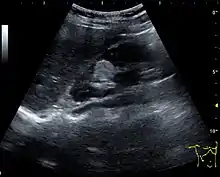

One of the primary indications for referral to US evaluation of the kidneys is evaluation of the urinary collecting system. Enlargement of the urinary collecting system is usually related to urinary obstruction and can include the pelvis, the calyces and the ureter. Hydronephrosis is seen as an anechoic fluid-filled interconnected space with enhancement within the renal sinus, and normally, the dilated pelvis can be differentiated from the dilated calyces.[1]

Several conditions can result in urinary obstruction. In both adults and children, masses, such as abscesses and tumors, can compress the ureter. In children, hydronephrosis can be caused by ureteropelvic junction obstruction, ectopic inserted ureter, primary megaureter and posterior urethral valve (Figure 13). In the latter, both kidneys will be affected. In adults, hydronephrosis can be caused by urolithiasis, obstructing the outlet of the renal pelvis or the ureter, and compression of the ureter from, e.g., pregnancy and retroperitoneal fibrosis. Urolithiasis is the most common cause of hydronephrosis in the adult patient and has a prevalence of 10%–15%.[1]

The hydronephrosis is typically graded visually and can be divided into five categories going from a slight expansion of the renal pelvis to end-stage hydronephrosis with cortical thinning (Figure 15). The evaluation of hydronephrosis can also include measures of calyces at the level of the neck in the longitudinal scan plane, of the dilated renal pelvis in the transverse scan plane and the cortical thickness, as explained previously (Figure 16 and Figure 17).[1]